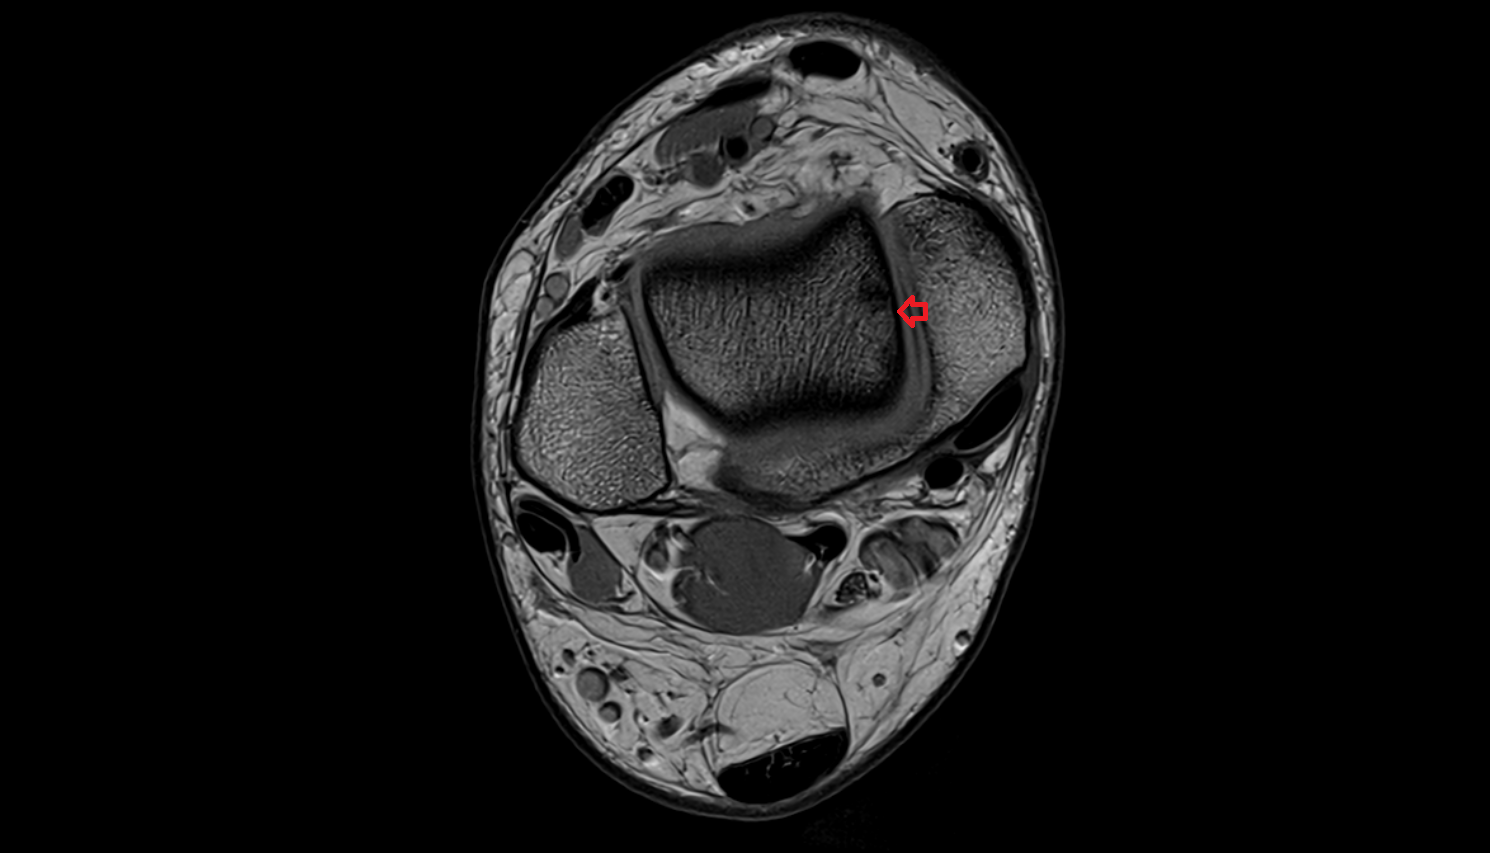

- Ankle joint

- Medial malleolus

- Lateral malleolus

- Talus

- Calcaneus

- Deltoid ligament complex

- Anterior talofibular ligament